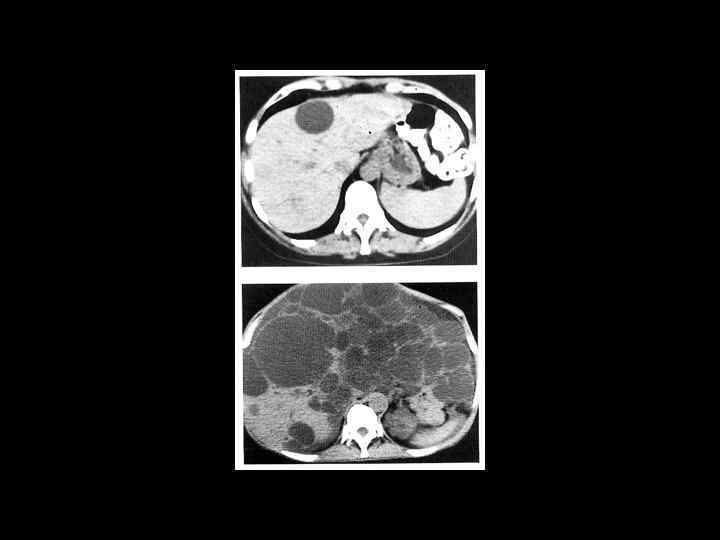

АКТУАЛЬНЫЕ ВОПРОСЫ РЕНТГЕНОЛОГИИ ЛУЧЕВАЯ ДИАГНОСТИКА ОЧАГОВЫХ ПОРАЖЕНИЙ ПЕЧЕНИ КАВЕРНОЗНАЯ ГЕМАНГИОМА Компьютерно-томографическая семиотика: - ограниченный участок пониженой плотности (до 50 -30 ед Н) - границы могут быть ровными, но нечеткими - после введения РКВ - характерный феномен усиления плотности от периферии к центру в течении нескольких минут после внутривенного введения РКВ

Клиническое наблюдение. Пациентка С. , 1953 г. р.

Та же пациентка